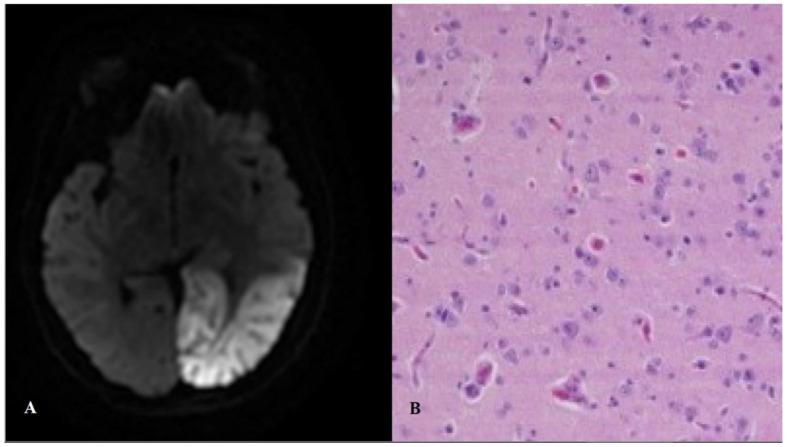

在过去十年中,线粒体疾病的遗传基础研究取得了显著进展。然而,与线粒体疾病相关的巨大表型变异性及其遗传学的独特特征,使线粒体疾病成为一组复杂的疾病。尽管特定的基因改变已与某些综合征表现相关联,但线粒体疾病的基因型-表型关系很复杂(单个突变可导致多种临床综合征,而不同的基因改变可导致相似的表型)。本综述将从临床而非分子角度重新审视线粒体疾病最常见的综合征表现。我们认为,近期大型多中心研究所采用并在此修订的新表型定义,可能有助于实现更统一的患者分类,这将对未来的自然史研究和临床试验有用。